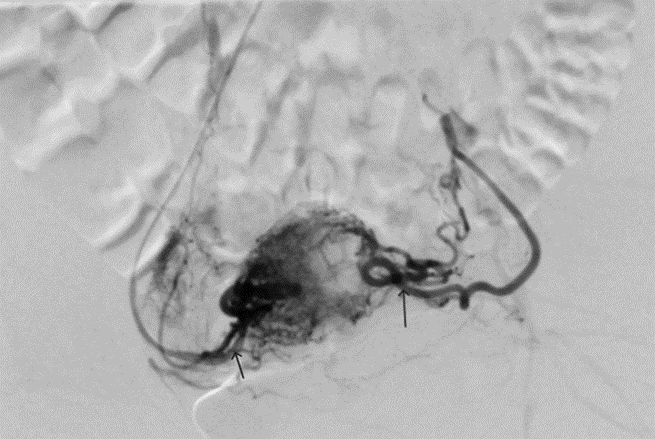

Stage 1 of surgical treatment: Abdominal aortography. Embolization of pelvic neoplasm vessels.

Under infiltration anesthesia with 1 ml of a 2% lidocaine solution, puncture and catheterization of the left radial artery was performed using a 5F introducer. Heparinization – 2500 IU of sodium heparin was administered intra-arterially (through the introducer). Using a hydrophilic 035 4F 150 cm catheter, sequential catheterization and angiography of the right and left uterine arteries (a. uterina), inferior vesical arteries (a. vesicalis inf.), and internal pudendal arteries (a. pudenda int.) were performed (Figs. 3 and 4).

Figure 3: Initial pelvic angiography. The right and left uterine arteries are well contrasted.

Figure 4: Initial pelvic angiography. Right and left internal genital arteries.